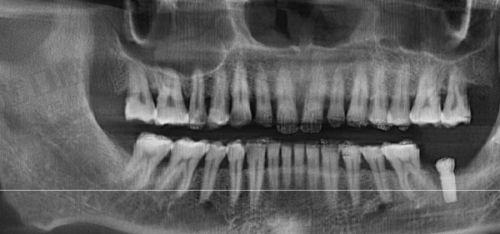

曾有一位老年患者,由于牙齿缺失多年,生活受到了较大的影响。患者在多家医院询问后,都对治疗方案不太满意。后来,患者找到了周毅医生。周毅医生经过详细的检查和评估,为患者制定了个性化的种植牙方案。在手术过程中,周毅医生凭借不错的技术,顺利完成了种植手术。术后,患者修复良好,牙齿功能得到了明显改善,生活质量也大大提高。患者对周毅医生的技术和服务非常满意,特意送来锦旗表示感谢。

周毅医生在种植牙领域有着极高的造诣。他是口腔种植和口腔修复两个首批国内临床重点专科的骨干成员,在医院先开展了穿颧种植等一系列高难度手术和治疗项目,折断种植体螺丝取出技术处于国内外领跑地位。